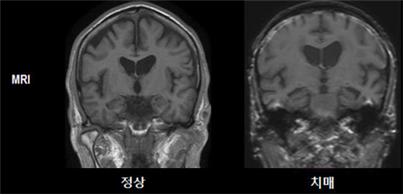

- 뇌 핵자기공명영상검사 (MRI)

뇌 MRI 검사는 치매와 노화성인지감퇴증의 원인이 되는 뇌 이상 소견을 사진으로 찍어 확인할 수 있는 진단검사로, 환자와 가족이 직접 환자의 뇌 상태를 확인할 수 있습니다. 뇌 MRI 검사는 부작용이 없고 통증도 없어 간단한 사전 설명만 들으면 노인들도 쉽게 받을 수 있는 안전한 검사입니다.